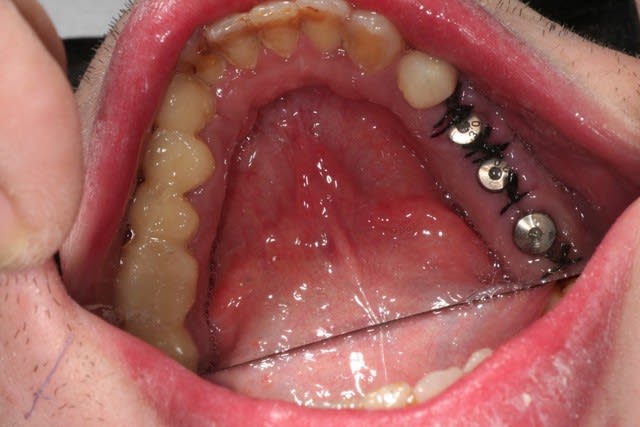

salut les petits clous...

voilà, je me suis remis un peu au boulot.

voici quelques images....

juste une remarque: pour l'instant je suis à la même DV.

ce matin, pose de trois implants.